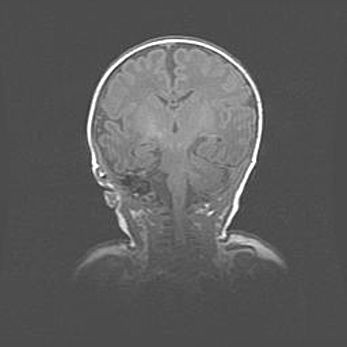

Мальформация Денди-Уокера. Киста задней черепной ямки.

Агенезия мозолистого тела.

Возраст: 2,5 месяца

Вес: 2420 г

Пол: женский

Окружность головы: 37 см

Срок гестации: 32 недели

Мальформация Денди—Уокера — редкий вид патологии ЦНС, представляющий собой врожденный порок развития каудального отдела ствола и червя мозжечка, ведущий к неполному раскрытию срединной (Мажанди) и латеральных (Лушка) апертур IV желудочка мозга. Для этогно синдрома характерна триада симптомов: гипотрофия червя мозжечка и/или полушарий мозжечка, кисты задней черепной ямки, гидроцефалия различной степени. В 70% случаев порок сочетается и с другими аномалиями головного мозга, в частности с агенезией мозолистого тела.